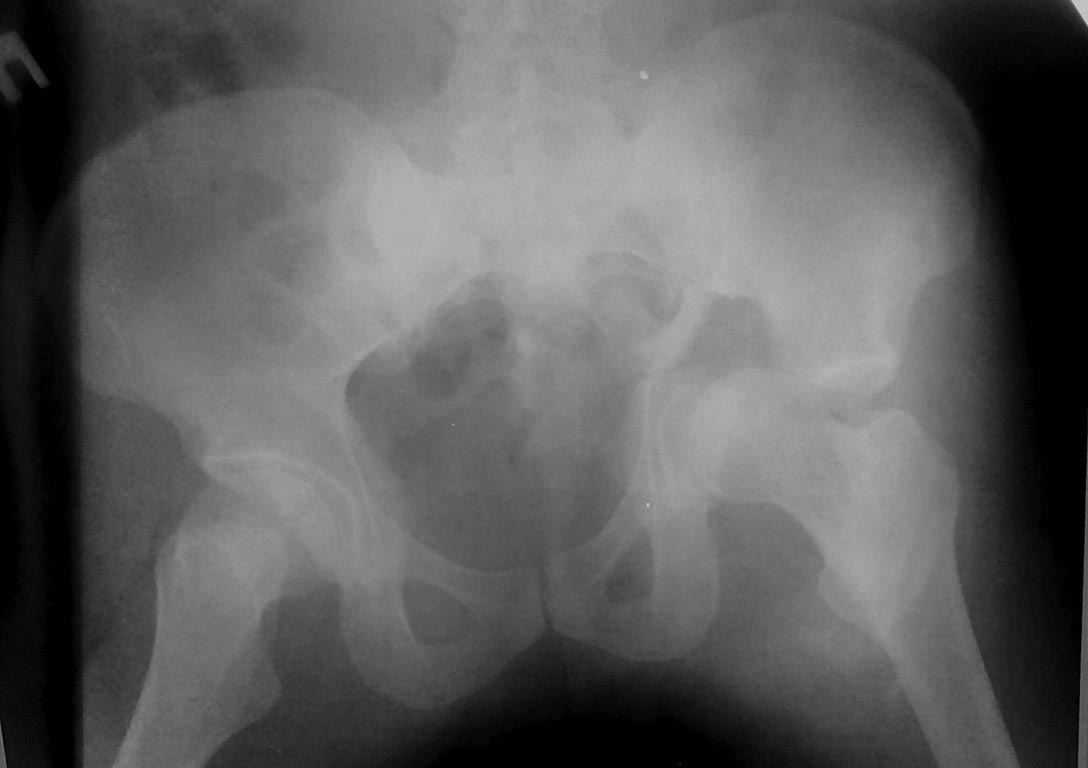

Это поперечный перелом вертлужной впадины, а не перелом таза.

И справа похоже тоже вертлужка сломанна .

Да, справа без смещения

Добрый день, уважаемые коллеги! Данный случай-полифокальное повреждение таза.Самый неблагоприятный вариант поперечно ориентированного перелома вертлужной впадины и ротационно нестабильное повреждение тазового кольца (КПС). Оперативное лечение- открытая реконструкция сустава и перкутанная фиксация КПС.

Вчера (17.10.17) снимок на месте палатным аппаратом.

Положение отломков прежнее.

Кт в день поступления прилагаю.